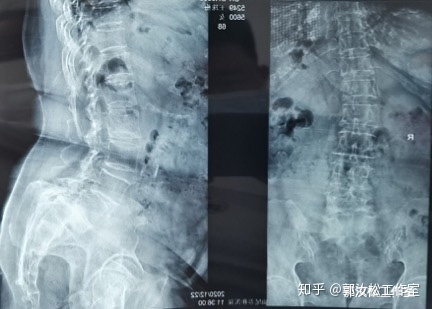

现病史: 患者10年前开始出现腰痛,无下肢不适,腰痛发作时自行外贴药膏或当地就诊药物治疗后缓解,未检查,未系统治疗。1年前患者腰痛反复发作,逐渐加重,同时伴有双下肢放射痛,走路逐渐跛行,平时仍自行外用药物外敷,或自行购买止痛药治疗,未到医院治疗。来诊前1周外院行腰椎X光检查提示腰椎退行性变,骨质疏松,L4、5椎体向前滑脱,L5达Ⅲ度滑脱。胃纳可,二便暂正常。

// 影像科 :X光片 /// 就诊当天影像学检查

1.腰椎滑脱(L4椎体向前I度,L5椎体向前Ⅲ度)

2.腰椎间盘突出症

3.老年性骨质疏松症